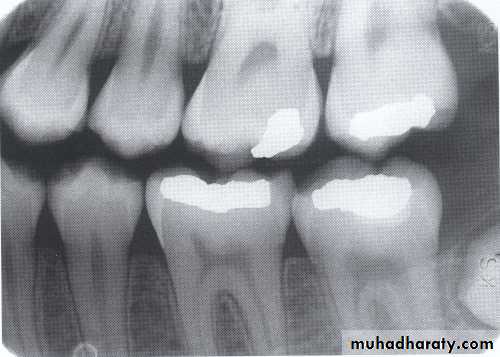

The bitewing radiograph is the view of choice for the evaluation of periodontal disease.

In addition to the periapical radiograph with paralleling technique could be used also, to evaluate the height of crestal bone is accurately recorded in relation to the tooth root.

A-Calculus:

It is a stone-like concretion that forms on the crown & roots of the teeth due to the calcification of bacterial plaque.

Its appear as radiopaque on the dental radiograph.

its either pointed or irregular radiopaque projection extending from the proximal root surface.

Calculus may be seen as a ring-like radiopacity encircling the cervical portion of the tooth.